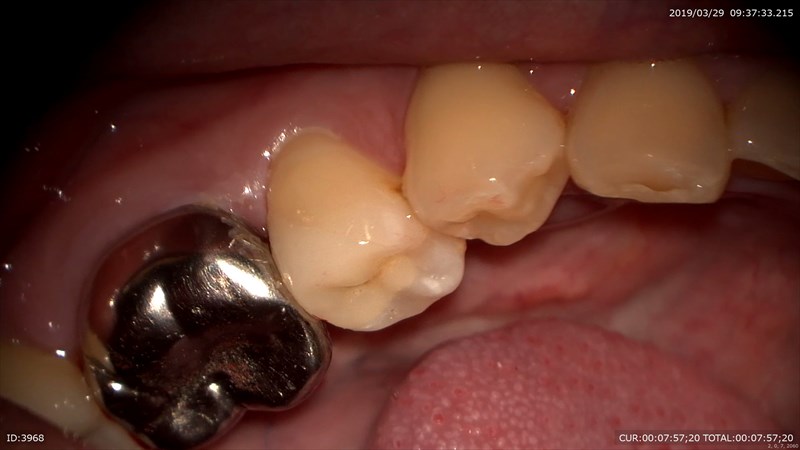

2ヶ月して問題なく自発痛も消えた!!

精密治療で神経を抜かずに済みました。

通院回数も3回です。